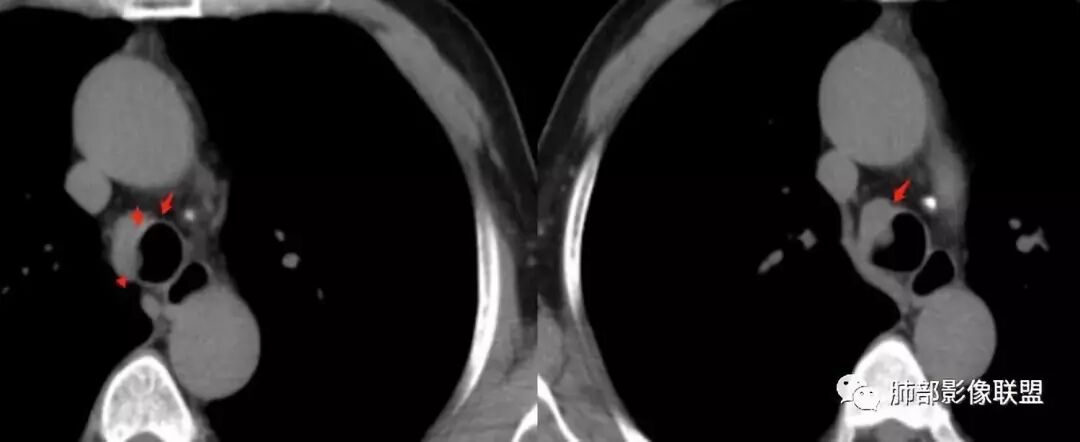

南边分析:针对本例,病灶跨气管壁内外生长,常规跨内外的有:恶性肿瘤为主,其次就是神经源性、平滑肌瘤;常规的思维:跨内外就要看结构的变化气管的优势在于软骨相对密度高,而且成C型

我们如何分析这个病例?冠状位:软骨密度稍高;病灶区软骨部分区域不连续,外围连续,提示病灶推移为主,不是破坏为主;如果破坏,应该这些软骨显示不清,移位不明显

病灶从软骨见推移开,跨内外,因此定在良性。恶性是侵犯,破坏为主,如果破坏,应该这些软骨显示不清,移位不明显,不是推移为主这例病变定在良性,我们就要考虑:1、软骨之间的平滑肌来源;2、神经源性

南边:

南边:高密度软骨在这两点上停了

南边:挤过去了,说明是从软骨间过去的

尘缘:@Shelia,部分是向前推,部分是向后推的。这个地方应该还有向后推的;肿物是从向前推与向后推这个间隙跨软骨的。

南边:需要用连续的窄窗观察。

病例小结      气管神经鞘瘤属于罕见的气管良性肿瘤,一般气管良性肿瘤或腔内或腔外生长的结节样改变,恶性肿瘤呈腔内外生长,但本例肿块向腔外生长,呈“冰山样改变”,即肿瘤的腔内部分较小而腔外部分较大,无周围组织侵犯。因此肿瘤腔内外生成不能作为鉴别气管良恶性肿块的绝对依据。        因此冠(矢)状位多平面观察、软骨是否破坏、气管壁有无增厚等细节观察,对于鉴别气管肿块良恶性有重要的参考性。